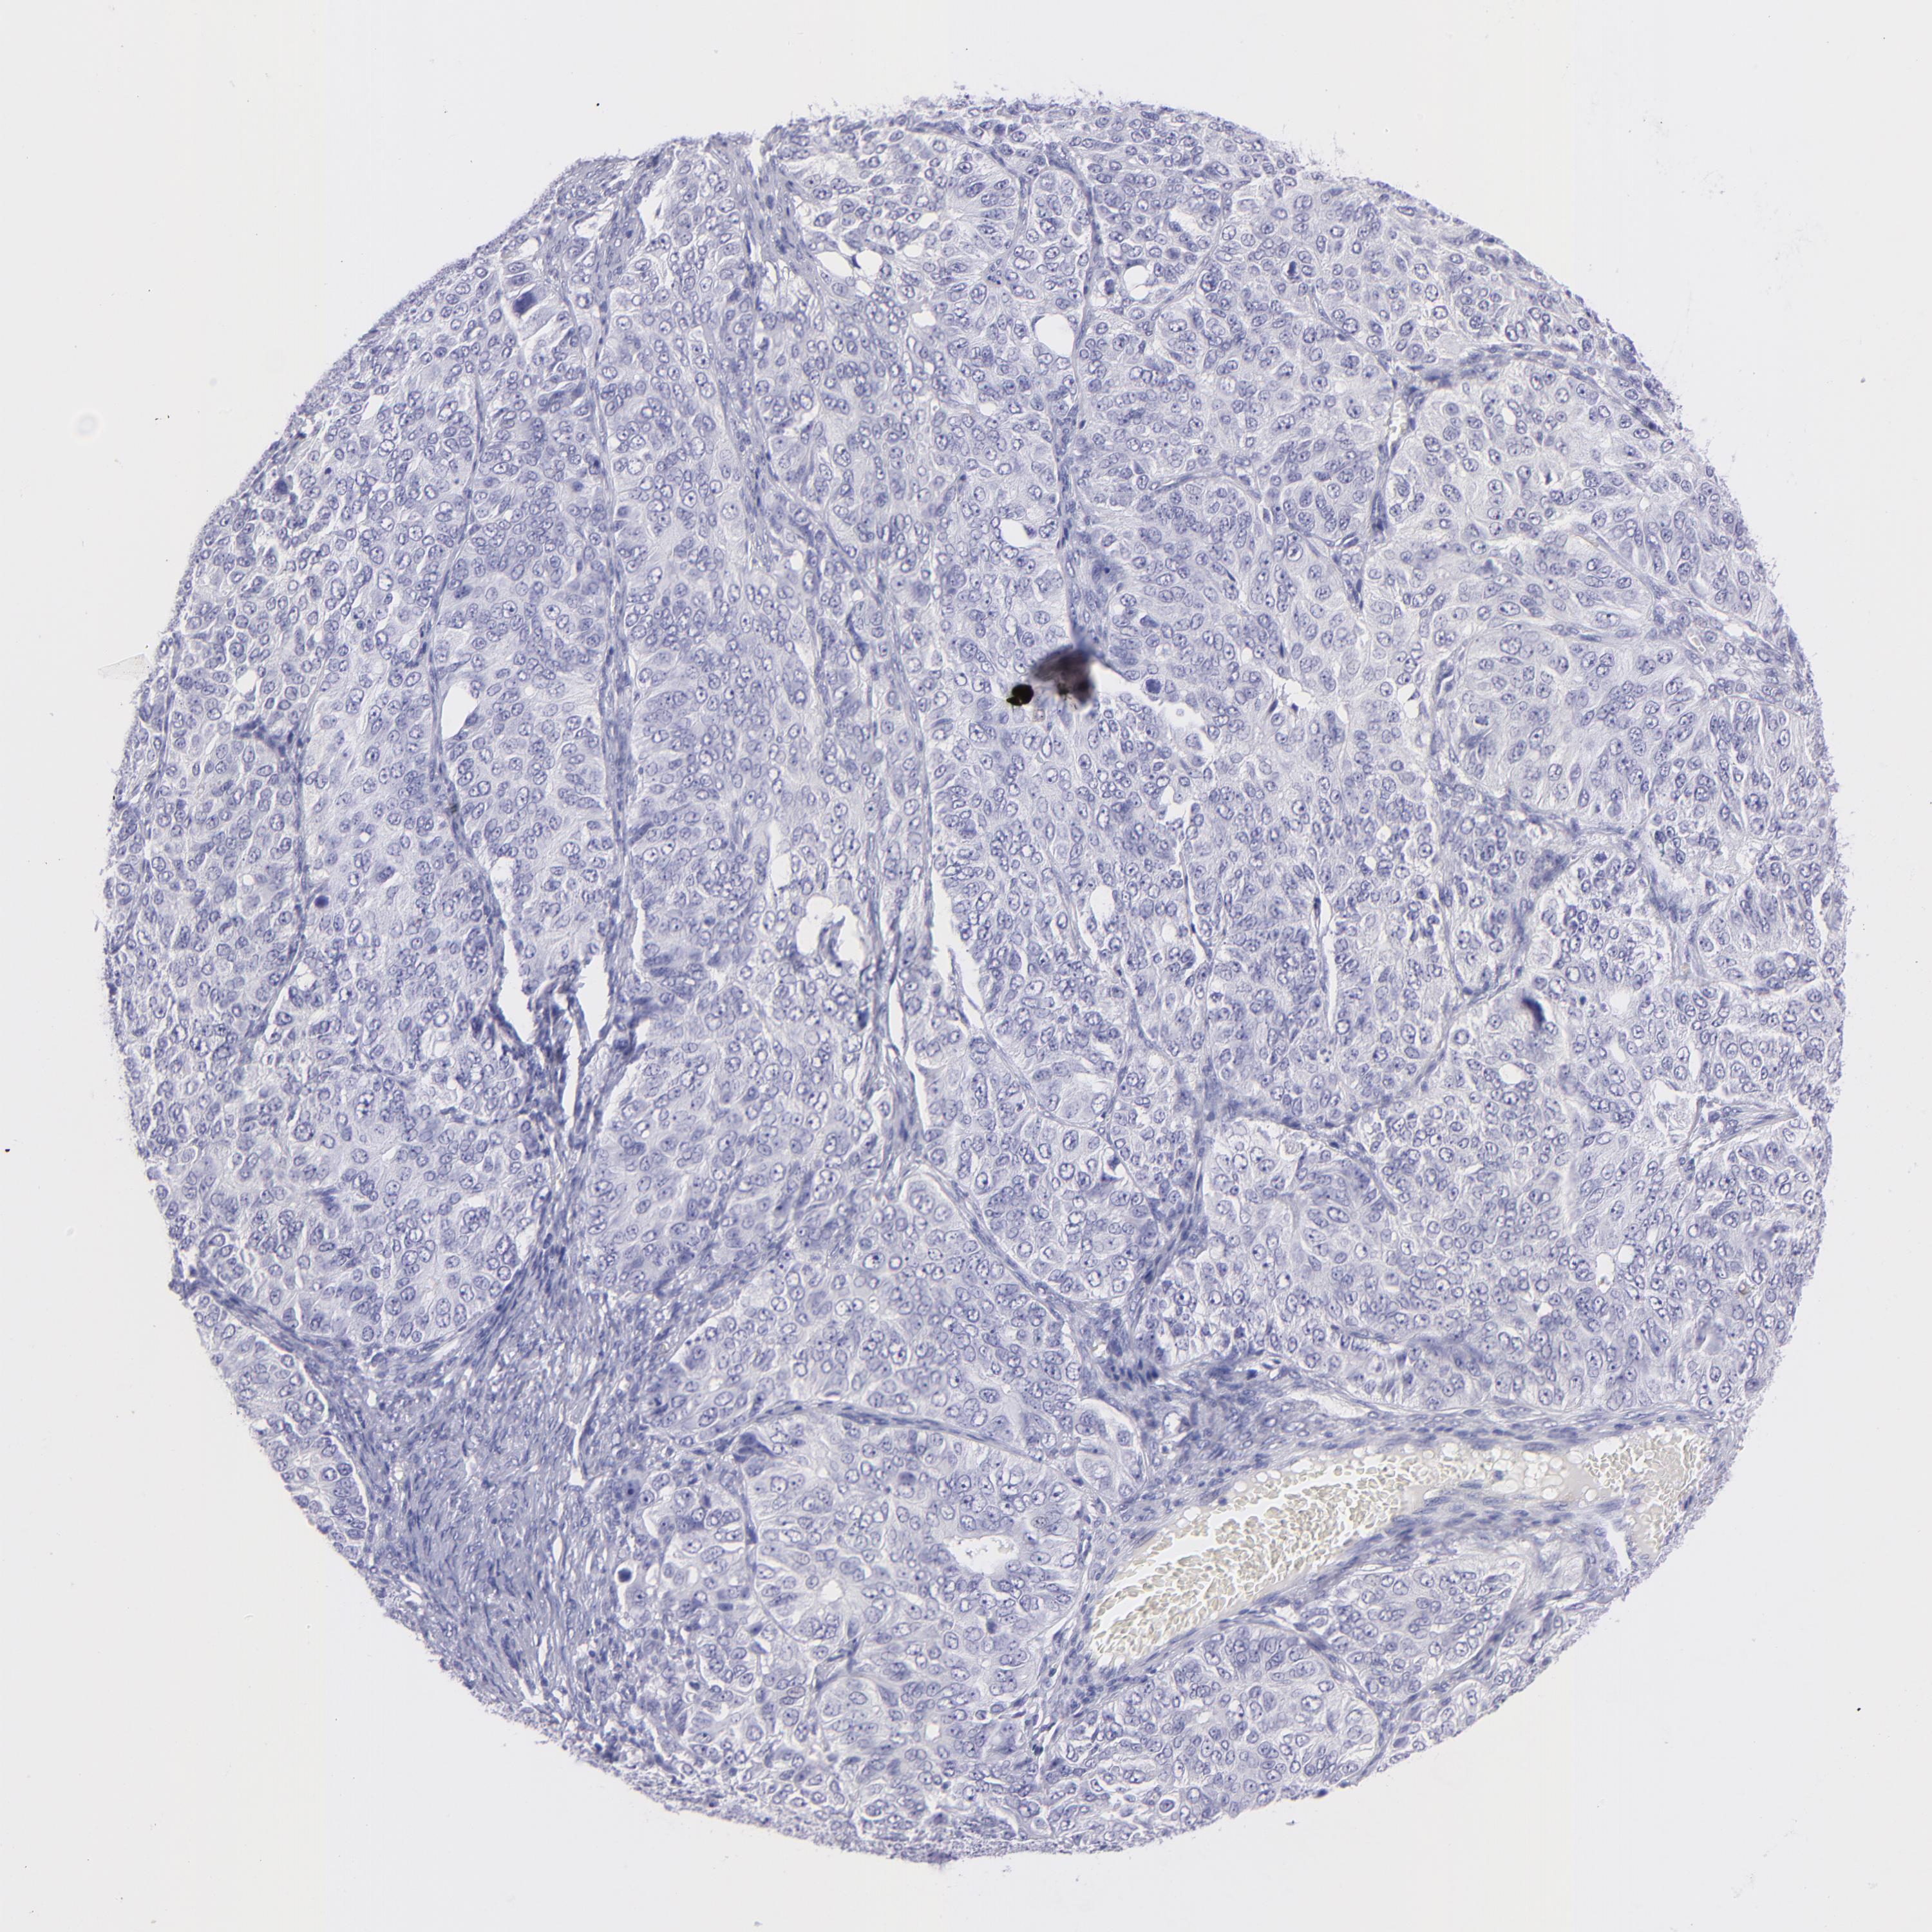

OVARIAN CANCER - Protein expressioni

A mouse-over function shows sample information and annotation data. Click on an image to view it in a full screen mode. Samples can be filtered based on level of antibody staining by selecting one or several of the following categories: high, medium, low and not detected. The assay and annotation is described here.

Note that samples used for immunohistochemistry by the Human Protein Atlas do not correspond to samples in the TCGA dataset.

Antibody stainingi

Antibody staining in the annotated cell types in the current human tissue is reported as not detected, low, medium, or high, based on conventional immunohistochemistry profiling in selected tissues. This score is based on the combination of the staining intensity and fraction of stained cells.

Each image is clickable and will lead to virtual microscopy that enables deeper exploration of all samples and also displays staining intensity scores, fraction scores and subcellular localization as well as patient and tissue information for each sample.

HPA023266

Cystadenocarcinoma, serous, NOS